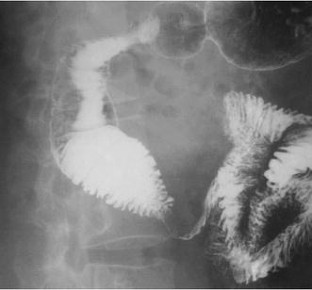

Fig. 1

Fig. 2

Fig. 3

Fig. 4

Fig. 5

Fig. 6

Fig. 7

Fig. 8